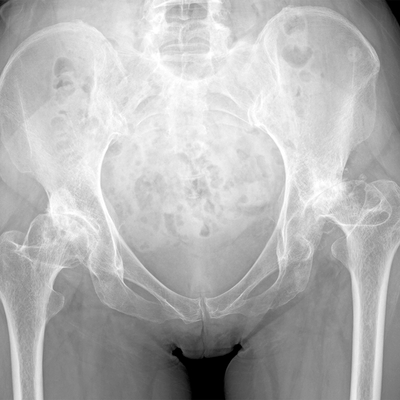

Click on an image below to view more info.